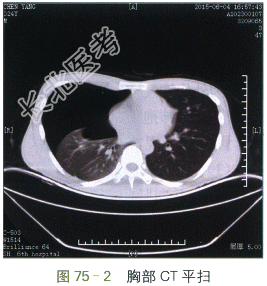

胸部X线正位片(见图75-1)显示右侧肺野大片无纹理透亮区,右侧肋间隙增宽、右侧膈肌低平,纵隔轻度左偏,右侧肋膈角变钝。胸部CT(见图75-2)提示右侧胸腔内大量气体影,右肺压缩不张。

读片分析:本例患者病史为突发右侧胸痛、急性起病。胸部X线正位片和胸部CT扫描提示右侧肺野外中带大片透亮无纹理区,右侧肺门可见压缩不张之肺组织,右侧肋间隙增宽、右侧膈肌低平,纵隔轻度左偏,右侧肋膈角变钝。所有征象均提示大量气胸的诊断。